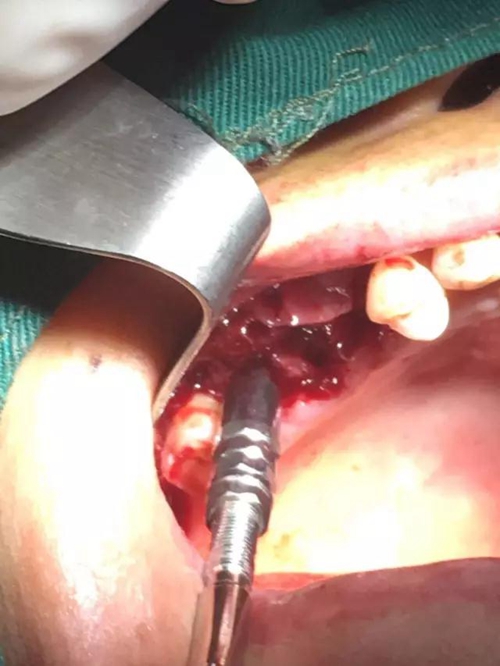

【病例分享】內(nèi)提,用自體骨柱,不用骨粉

1.jpg